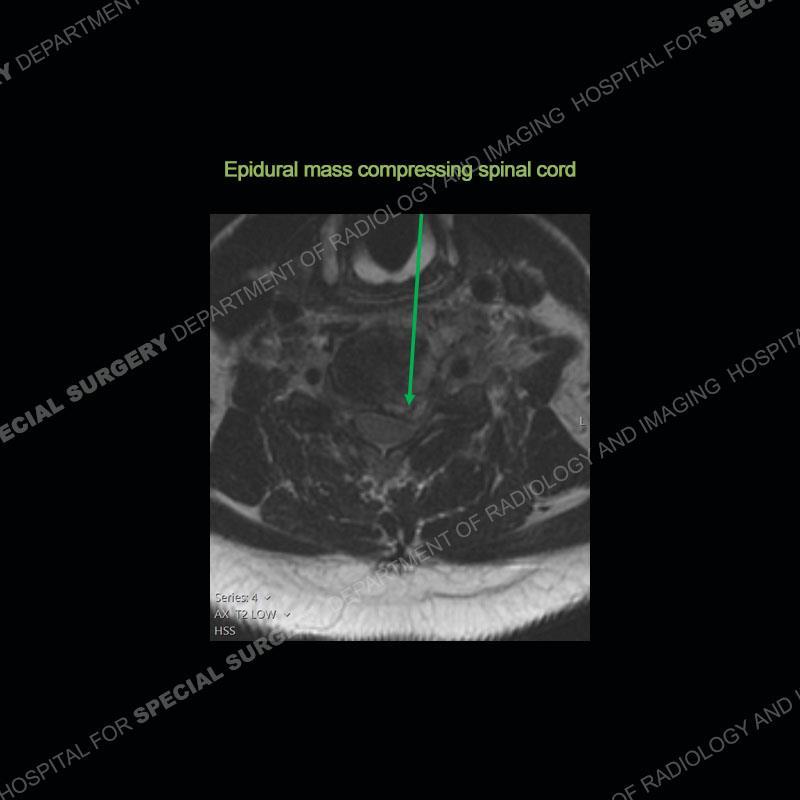

The radiographs demonstrate a prevertebral soft tissue fullness centered at C5-C6 that persists even on extension. There is a slight loss of disc height at C5-C6. The CT more readily shows the prevertebral soft tissue swelling at C5C6 where there is a punctate focus of gas. On the MRI, there is a marked amount of edema and a heterogeneous collection in the prevertebral soft tissue at C5-C6. Edema is present of the C5 and C6 vertebral bodies with a loss of the normal architecture about the disc space. A heterogeneous epidural collection has formed that causes compression of the spinal cord asymmetric to the left side and also precipitates severe left sided neural foraminal stenosis.

Diagnosis: Spontaneous Retropharyngeal Abscess (RPA) with Discitis/Osteomyelitis, Epidural Abscess, and Cord Compression

Spontaneous RPA in the non-immunocompromised, adult population is an extremely rare occurrence. RPA most frequently occurs in young children and most typically after a URI. It may be associated with torticollis in Grisel syndrome. In the adult population, the pathomechanism is not well understood with some suggesting a hematogenous spread or perhaps a seeding from the adjacent aerodigestive tract. The abscess as in this case can extend to involve the vertebral column and then the neural elements. At times, this process can be treated with antibiotic therapy alone but when there are neurologic symptoms and especially progression of neurologic symptoms, surgical intervention is warranted. In this case, given the extent of the process and the patient’s clinical situation, a corpectomy with fusion was performed in addition to antibiotics.